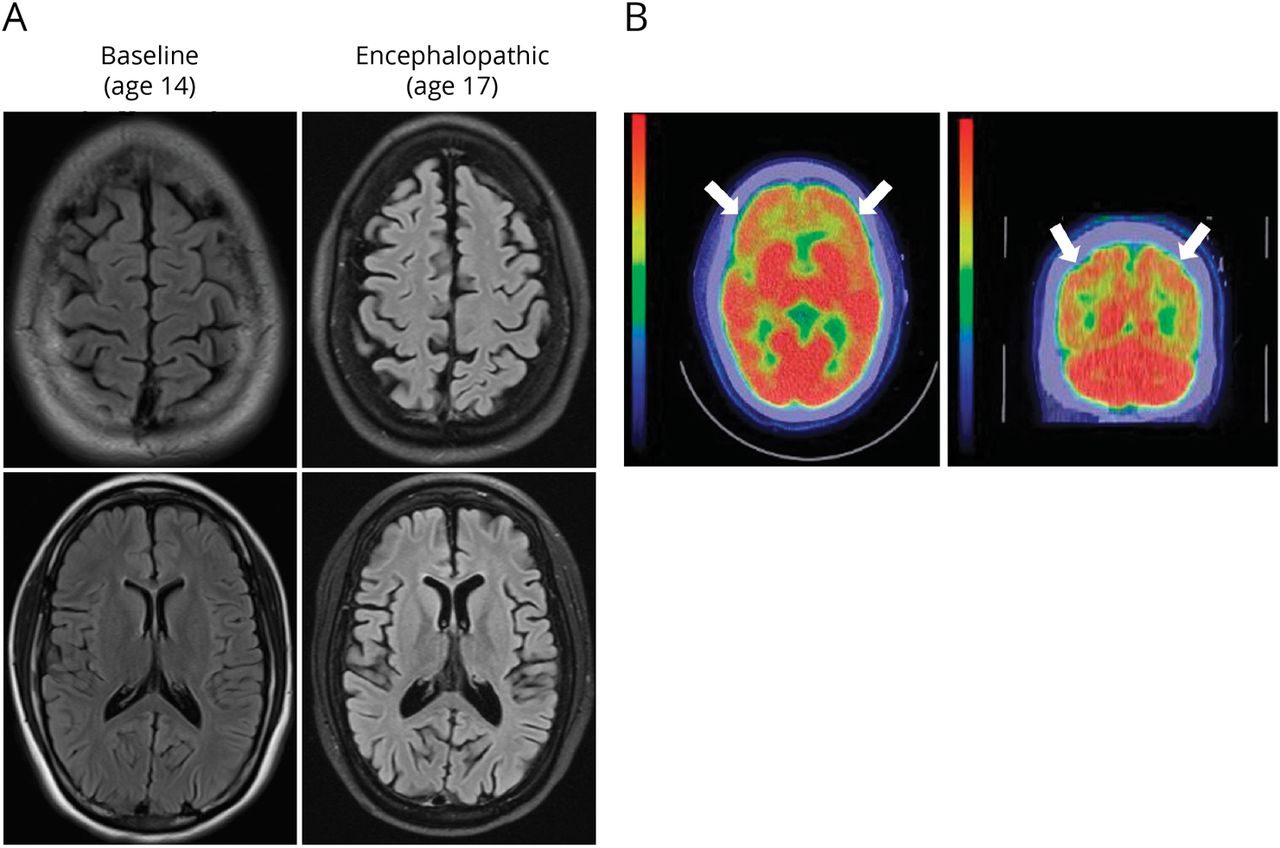

例子(一)轴向片大脑T2-fluid-attenuated反转恢复核磁共振成像序列在基线(14岁),在脑病发作(16岁)。图片展示进步皮质和中央萎缩与神经退化一致。(B)与f - 18 fluoro-2-deoxyglucose磁共振成像的大脑执行。图片展示了相对对称的异常代谢减退双边frontoparietal(白色箭头)和双边颞区域(没有显示)。

当年晚些时候,在等待whole-exome测序结果,病人敏锐地拒绝,考入医院5天后改变精神状态。具体来说,她每天睡16 +小时,有限的,莫名其妙的演讲和与洗澡和打扮越来越难。她可以回答一些是非问题,但在执行一些简单的指令不一致。神经系统检查发现完整的颅神经,正常的肌肉和力量,完整的感觉,对称反射,将足底。她需要帮助,她的步伐是缓慢和洗牌。视频脑电图得到因为关心nonconvulsive癫痫持续状态。脑电图是特异性的有轻微混乱背景没有明显的后主导节奏。有过度的θ和δ在额叶和颞叶的活动。孤立的独立焦峰值出现在额叶和颞区域,这促使Keppra治疗。脑部MRI显示弥漫性肺实质损失相比,14岁时,她最初的核磁共振显示进步的神经退化(图,一个)。CT PET成像显示相对对称的异常代谢减退双边frontoparietal和双边颞区域,相对保留其他大脑区域(图B)。她又经验与丙种球蛋白治疗自身免疫性脑炎,适度提高她的症状。急性住院病人康复出院。